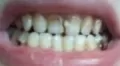

Я нашла у себя кариес на двух передних зубах. И хочу поставить пломбу. Одни мне говорят что если поставить пломбу, то зуб начнет гнить и пломбу будет сильно видно, а другие говорят, что пломбу не отличить от настоящего зуба. Скажите что делать?

Добрый день. Уважаемая Светлана, скорей всего вы не правильно все поняли, так как зуб не может гнить при грамотной установки пломбы, скорее всего, есть какая-та другая причина. Если вы попадете к грамотному терапевту и после снятия кариозных отложений сделаете красивую реставрацию, то все будет отлично и никто не отличит пломбу от своего зуба. Но повторяюсь, вам необходимо обратиться к терапевту с опытом и с навыками не просто установки пломб, а с навыками и умением реставрировать коронковую часть зуба. Всего вам доброго.

P.S Хочу добавить, что реставрация передних зубов очень тонкая и кропотливая работа и требует опыта в изготовлении в полости рта терапевтических виниров (метод реставрации путем перекрытия всей фронтальной части зуба для достижения высокой эстетики).